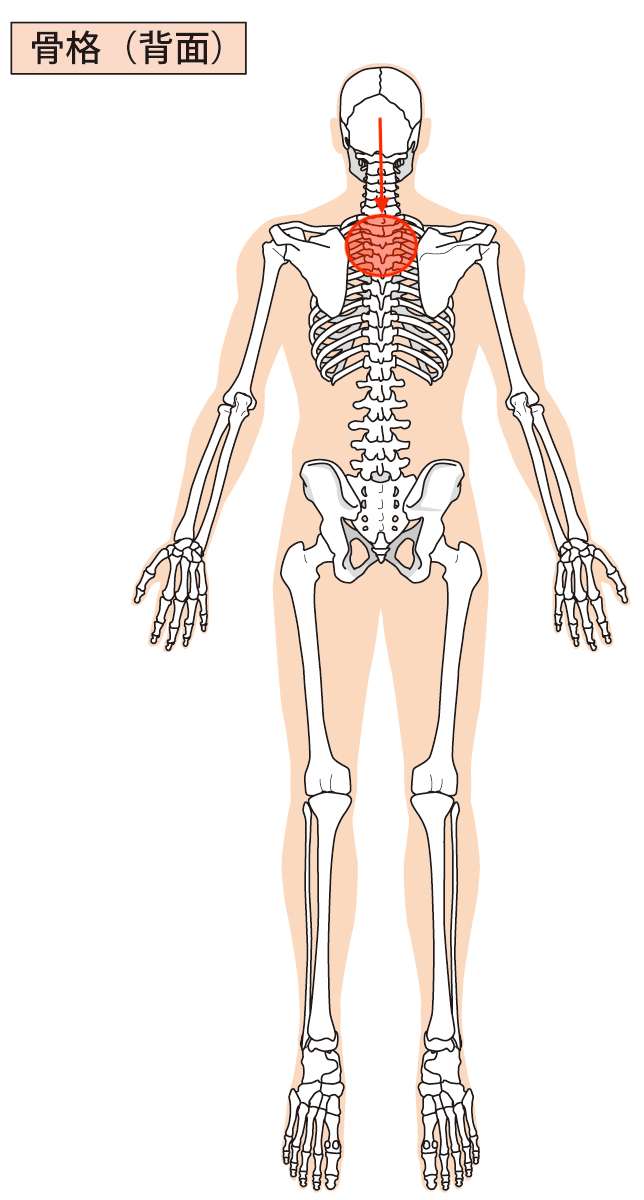

図で言うとこんな感じです。

一枚目が前から見た図と、二枚目が後ろから見た図で表しています。

図をご覧いただくと、当院にご相談くださった方の場合、赤丸の位置に痛みを感じており、その部分が痛く、また背骨の動きが制限されていました。

そして、赤の矢印が確認できるかと思いますが、その矢印の方向が赤丸を指していることがわかると思います。

この赤の矢印の方向に向かって張力(引っ張られる力)が加わっており、目の付近が赤丸の方向へ引っ張られている様子を表しています。

こんなふうにして目の奥、目の神経系や目の血管系を含めた組織が持続的に引っ張られるようなストレスを受けると、「目の痛みや目のかすみ」などの目の症状を感じることになります。

今回ご紹介させていただいた方も同じで、そういった引っ張られるようなストレスがかかることにより、目に負担となり、「目の奥が痛い」という症状の出現につながったのではないか?ということが考えられました。